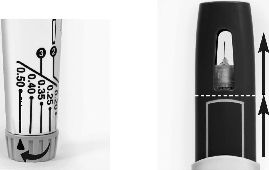

• Ayar düğmesini çevirerek size reçetelenen doza getirin (bkz. Şekil 8). Çevirirken klik sesleri duyabilirsiniz.

Not: Doz ayar düğmesini çevirirken iğne kılıfı otomatik olarak YUKARIYA GİDECEKTİR (bkz. Şekil 9). Enjeksiyondan önce doz ayar düğmesini çevirerek herhangi bir dozu artırabilir veya azaltabilirsiniz.

Şekil 8 Şekil 9